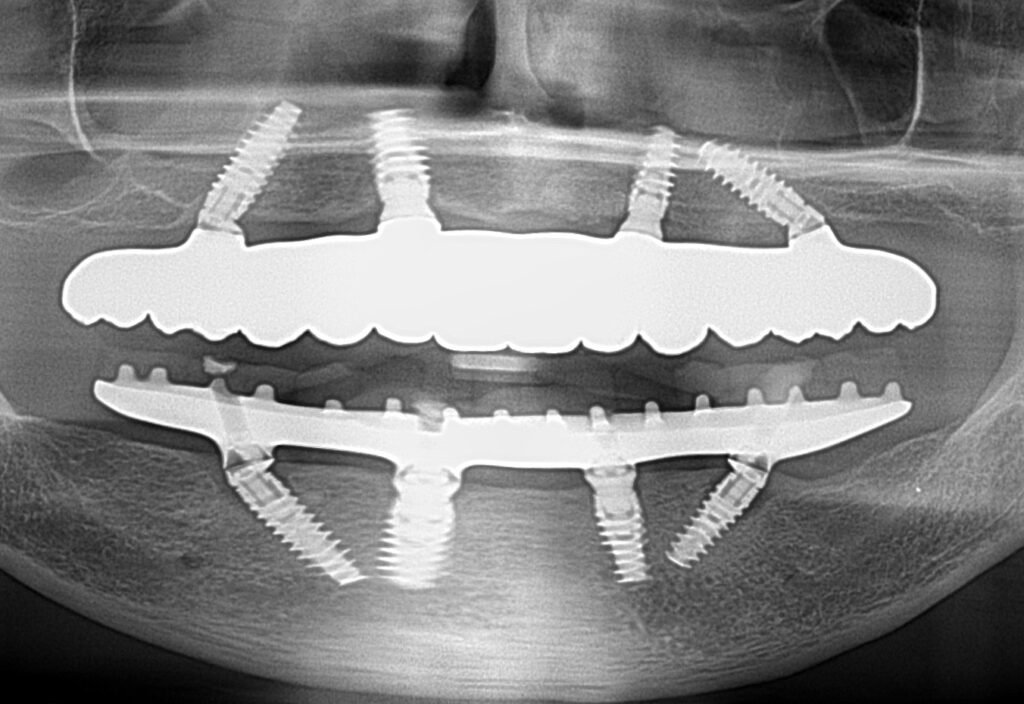

A selection of full arch fixed implant bridge patients after 5 years of wear

Oral Surgeons – Dr Han Choi, Dr Sam Goldsmith, Dr Rajiv Rajpal NSOMS

Prosthodontist – Dr Alan Payne NSOMS/Northland Prosthodontics

Dental technicians – Hosaka Takashi, DT Denture Design, Auckland, CJ Park, Project Dentistry, Auckland and Osteon Medical, Melbourne, Australia.